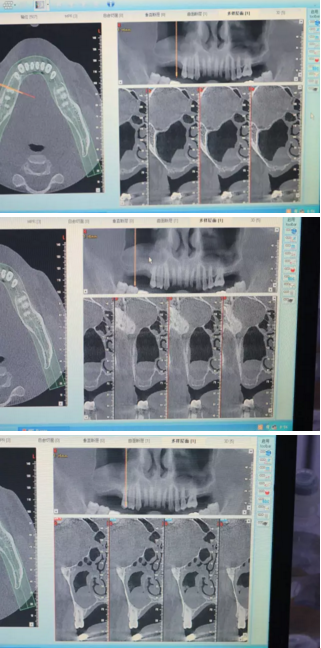

【病例分享】上頜竇大囊腫外提升